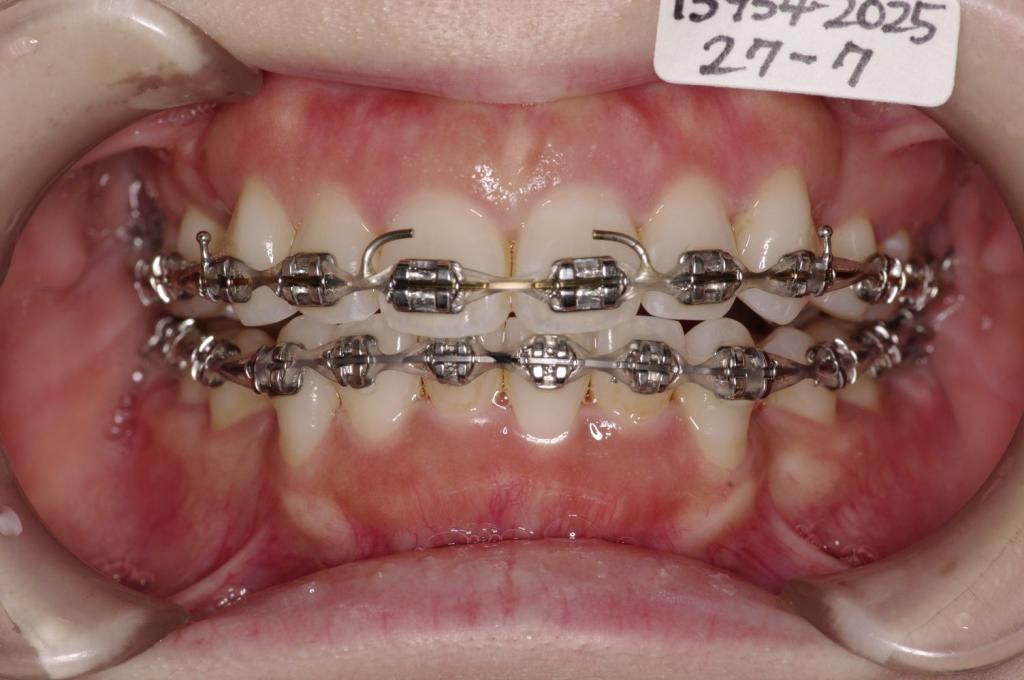

装置の種類及び治療法 診断:上下顎前突

治療方法および装置:マルチブラケット装置

High pull J-hook headgear

抜歯:右上84 /左上48

右下84 /左下48

装置写真

治療前

前歯、出っ歯・開咬の矯正治療前口内写真NO.1103